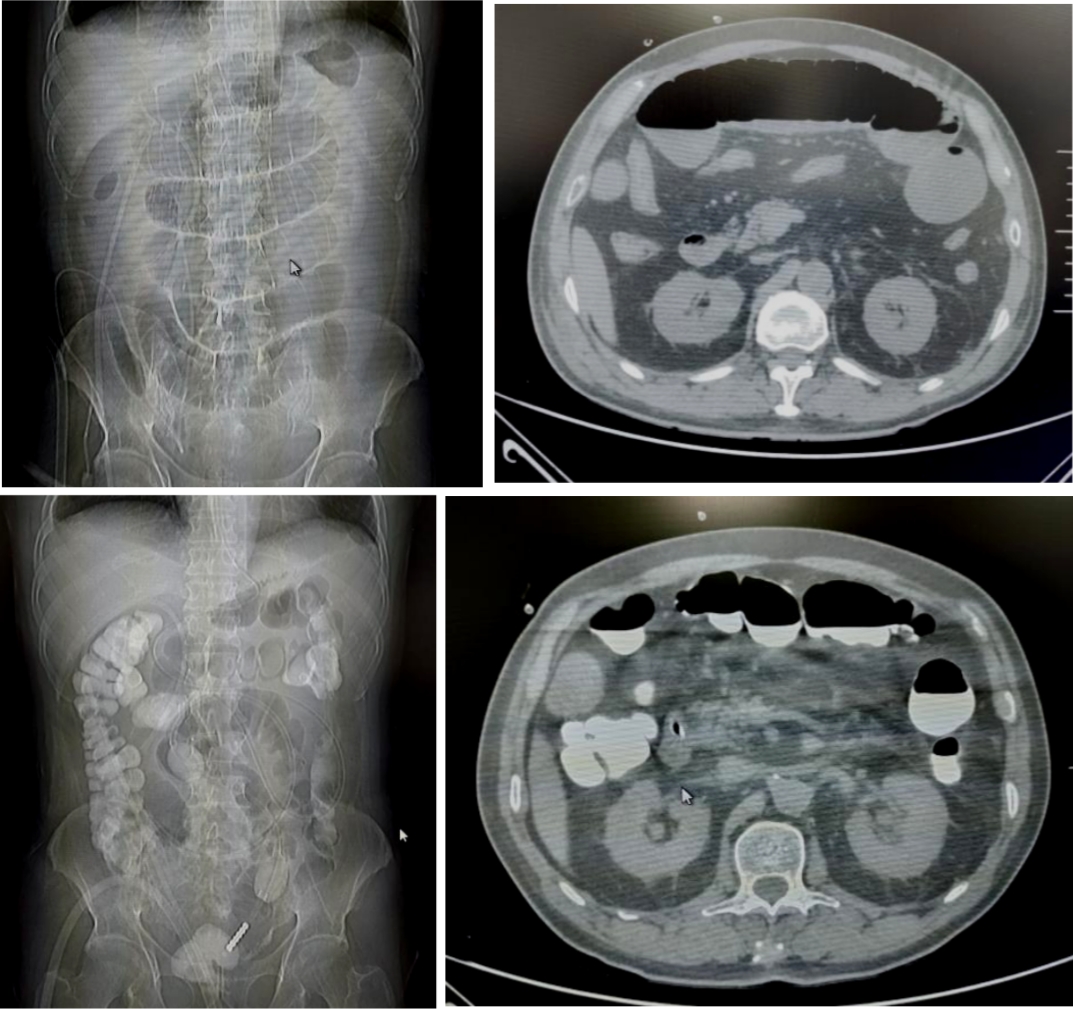

71岁的患者刘先生,因行膀胱癌根治术、回肠代膀胱术出现肠梗阻。后在我院放射介入室行DSA引导下经鼻肠梗阻导管置入术,术后当日患者腹胀较前明显缓解,术后第6天患者排气、排便,肠管恢复通畅,拔除肠梗阻导管。

病例2

18岁的患者叶女士,因行阑尾穿孔导致盆腔脓肿后出现肠梗阻。后在我院放射介入室行DSA引导下经鼻肠梗阻导管置入术,术后当日患者腹胀较前明显缓解,术后第3天患者排气、排便,肠管恢复通畅,拔除肠梗阻导管。